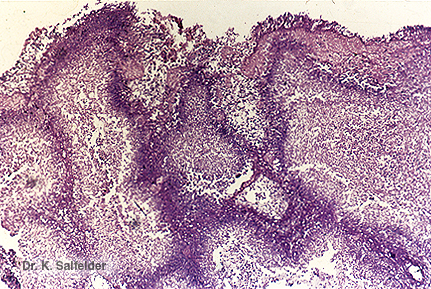

Abb. 21J,2: Kavitaeres Candidom

Bei dieser Vergroesserung und mit dieser Faerbung sind die Pilze des "fungus balls" kaum zu erkennen. HE-Faerbung